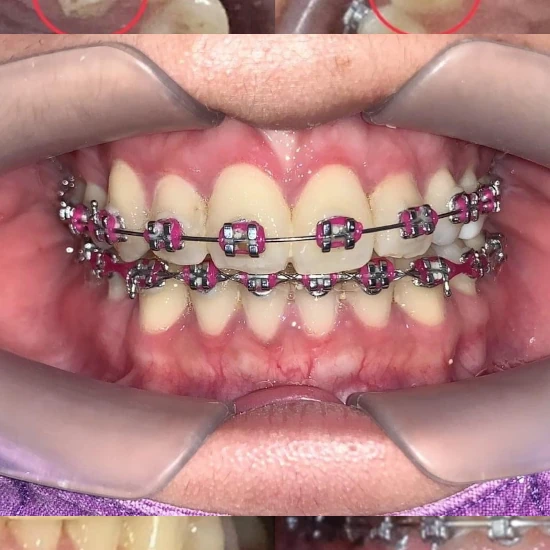

ลูกค้าจัดฟันทำฟัน

เปลี่ยนสียางได้

| จัดฟันแบบโลหะ | 36,000-45,000/เซต |